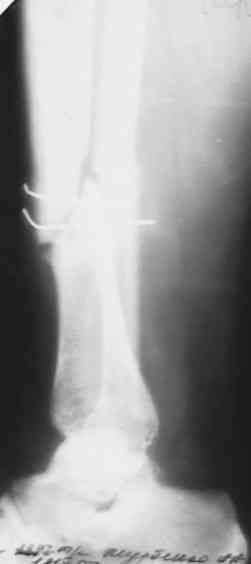

сегодня поставил аппарат , проблем не было . спицы убрал , но пришлось рубить малоберцевую из маленького разреза . Постепенно восстановлю длину и ось . как получится покажу снимки .Спасибо огромное всем коллегам ,откликнувшимся на вопрос !